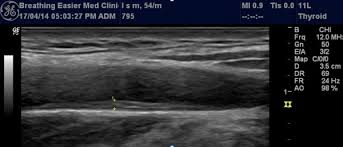

경동맥 초음파 검사는 일반적으로 간단한 과정으로 이루어져 있습니다. 환자는 편안한 자세로 누운 채로 검사가 시작됩니다. 검사자는 초음파 기계를 사용하여 경동맥의 위치에 젤을 바르고, 초음파 송신기를 적용하여 이미지를 생성합니다. 이 과정에서 환자는 특수한 느낌이나 통증을 느끼지 않아야 하며, 검사는 보통 30분 정도 소요됩니다.

검사 후 생성된 이미지를 바탕으로 의사는 동맥의 두께, 협착 여부, 혈전 존재 여부 등을 평가하여 다양한 질병의 가능성을 진단하게 됩니다. 이러한 과정은 고도화된 기술을 활용하여 매우 정확하게 이루어지므로, 정기적인 검사는 매우 중요합니다.